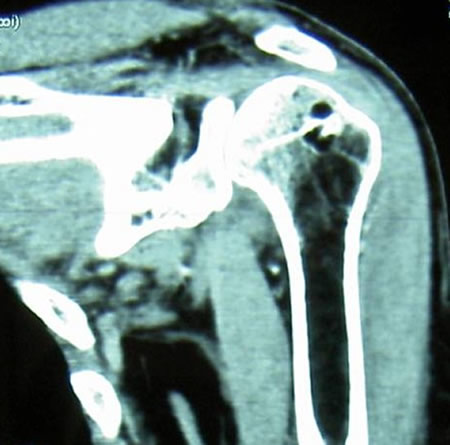

The frozen scapulothoracic space : A pathognomonic symptom of peri scapular fibromatosis.

The stiffness of the shoulder can result of many illness. Nevertheless, we observed a severe stiffness of the scapulo thoracic space only in fibromatosis.

In 10 of 11 patients with peri-scapular fibromatosis, the passive mobility of the scapulo thoracic space was severely impaired (less than 20°).

In metastases, sarcoma and other soft tissue tumour the passive mobility of the scapulo-humeral joint is usually preserved and the mobility of the scapulothoracic space is always normal even in very huge tumours.

The frozen scapulo thoracic is a specific symptom of peri scapulo thoracic fibromatosis.